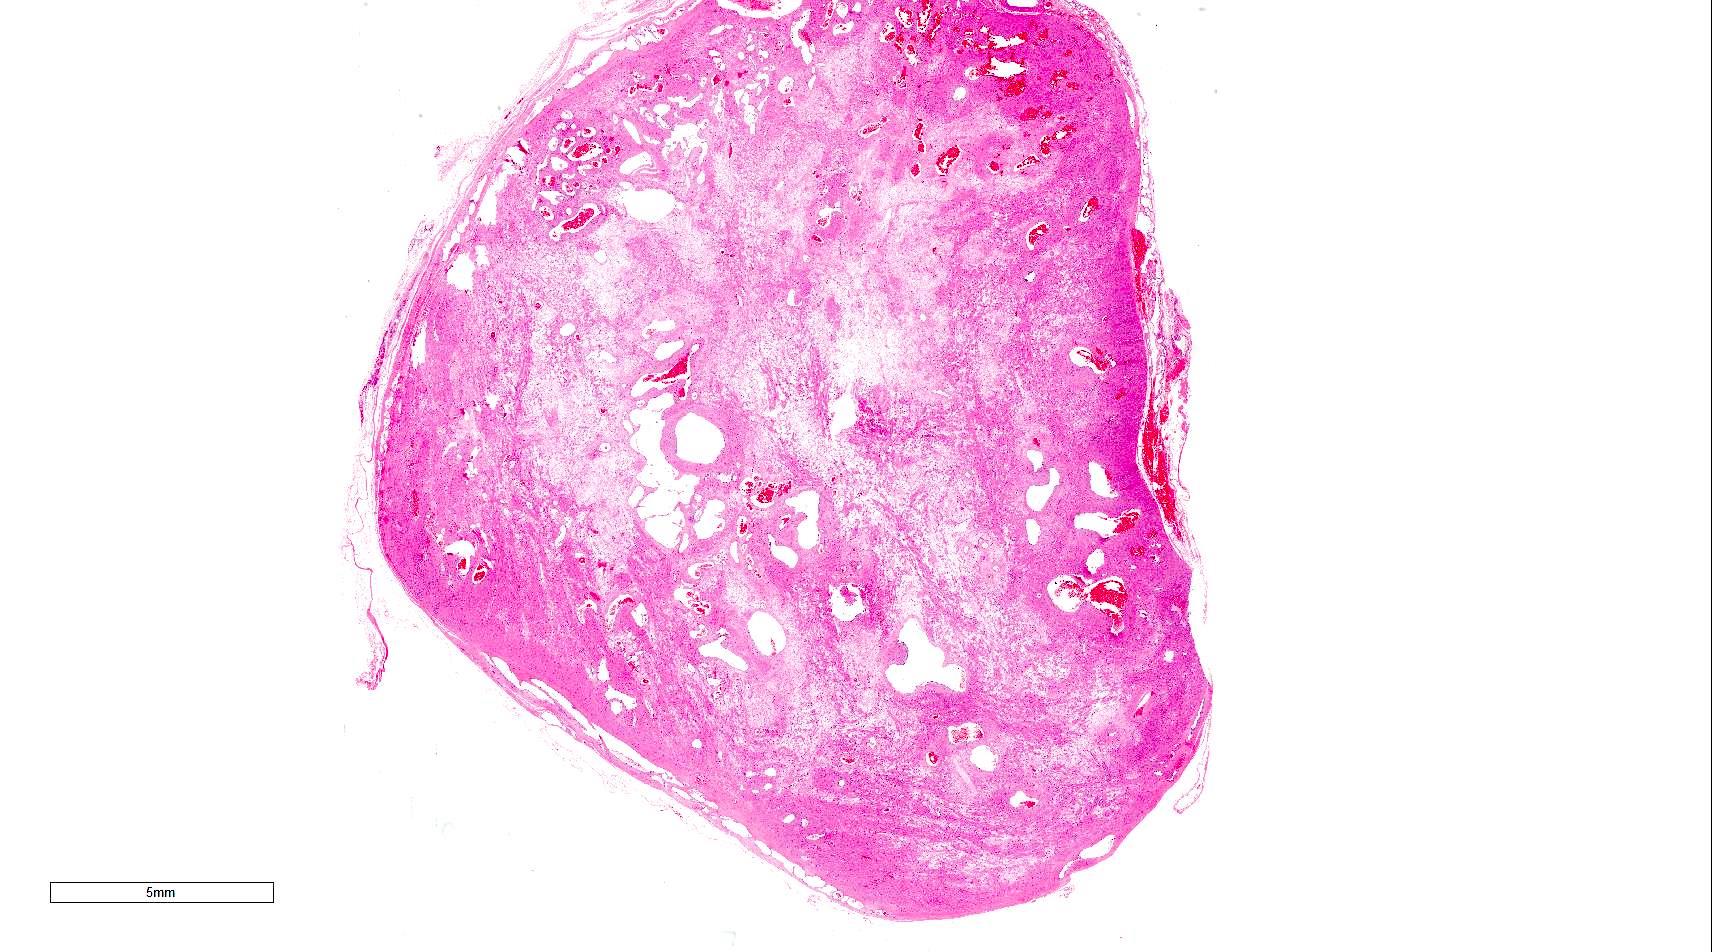

Gross description

- Sharply demarcated, spherical, gray-white or brown tumor

- Usually measuring less than 2 cm in diameter in approximately 80% of cases

- Reference: Cancer 1984;54:126

Microscopic (histologic) description

- Encapsulated proliferation of eosinophilic smooth muscle cells with minimal nuclear pleomorphism

Microscopic (histologic) images

Contributed by Ohoud Aljarbou, M.D., Jijgee Munkhdelger, M.D., Ph.D. and Andrey Bychkov, M.D., Ph.D.